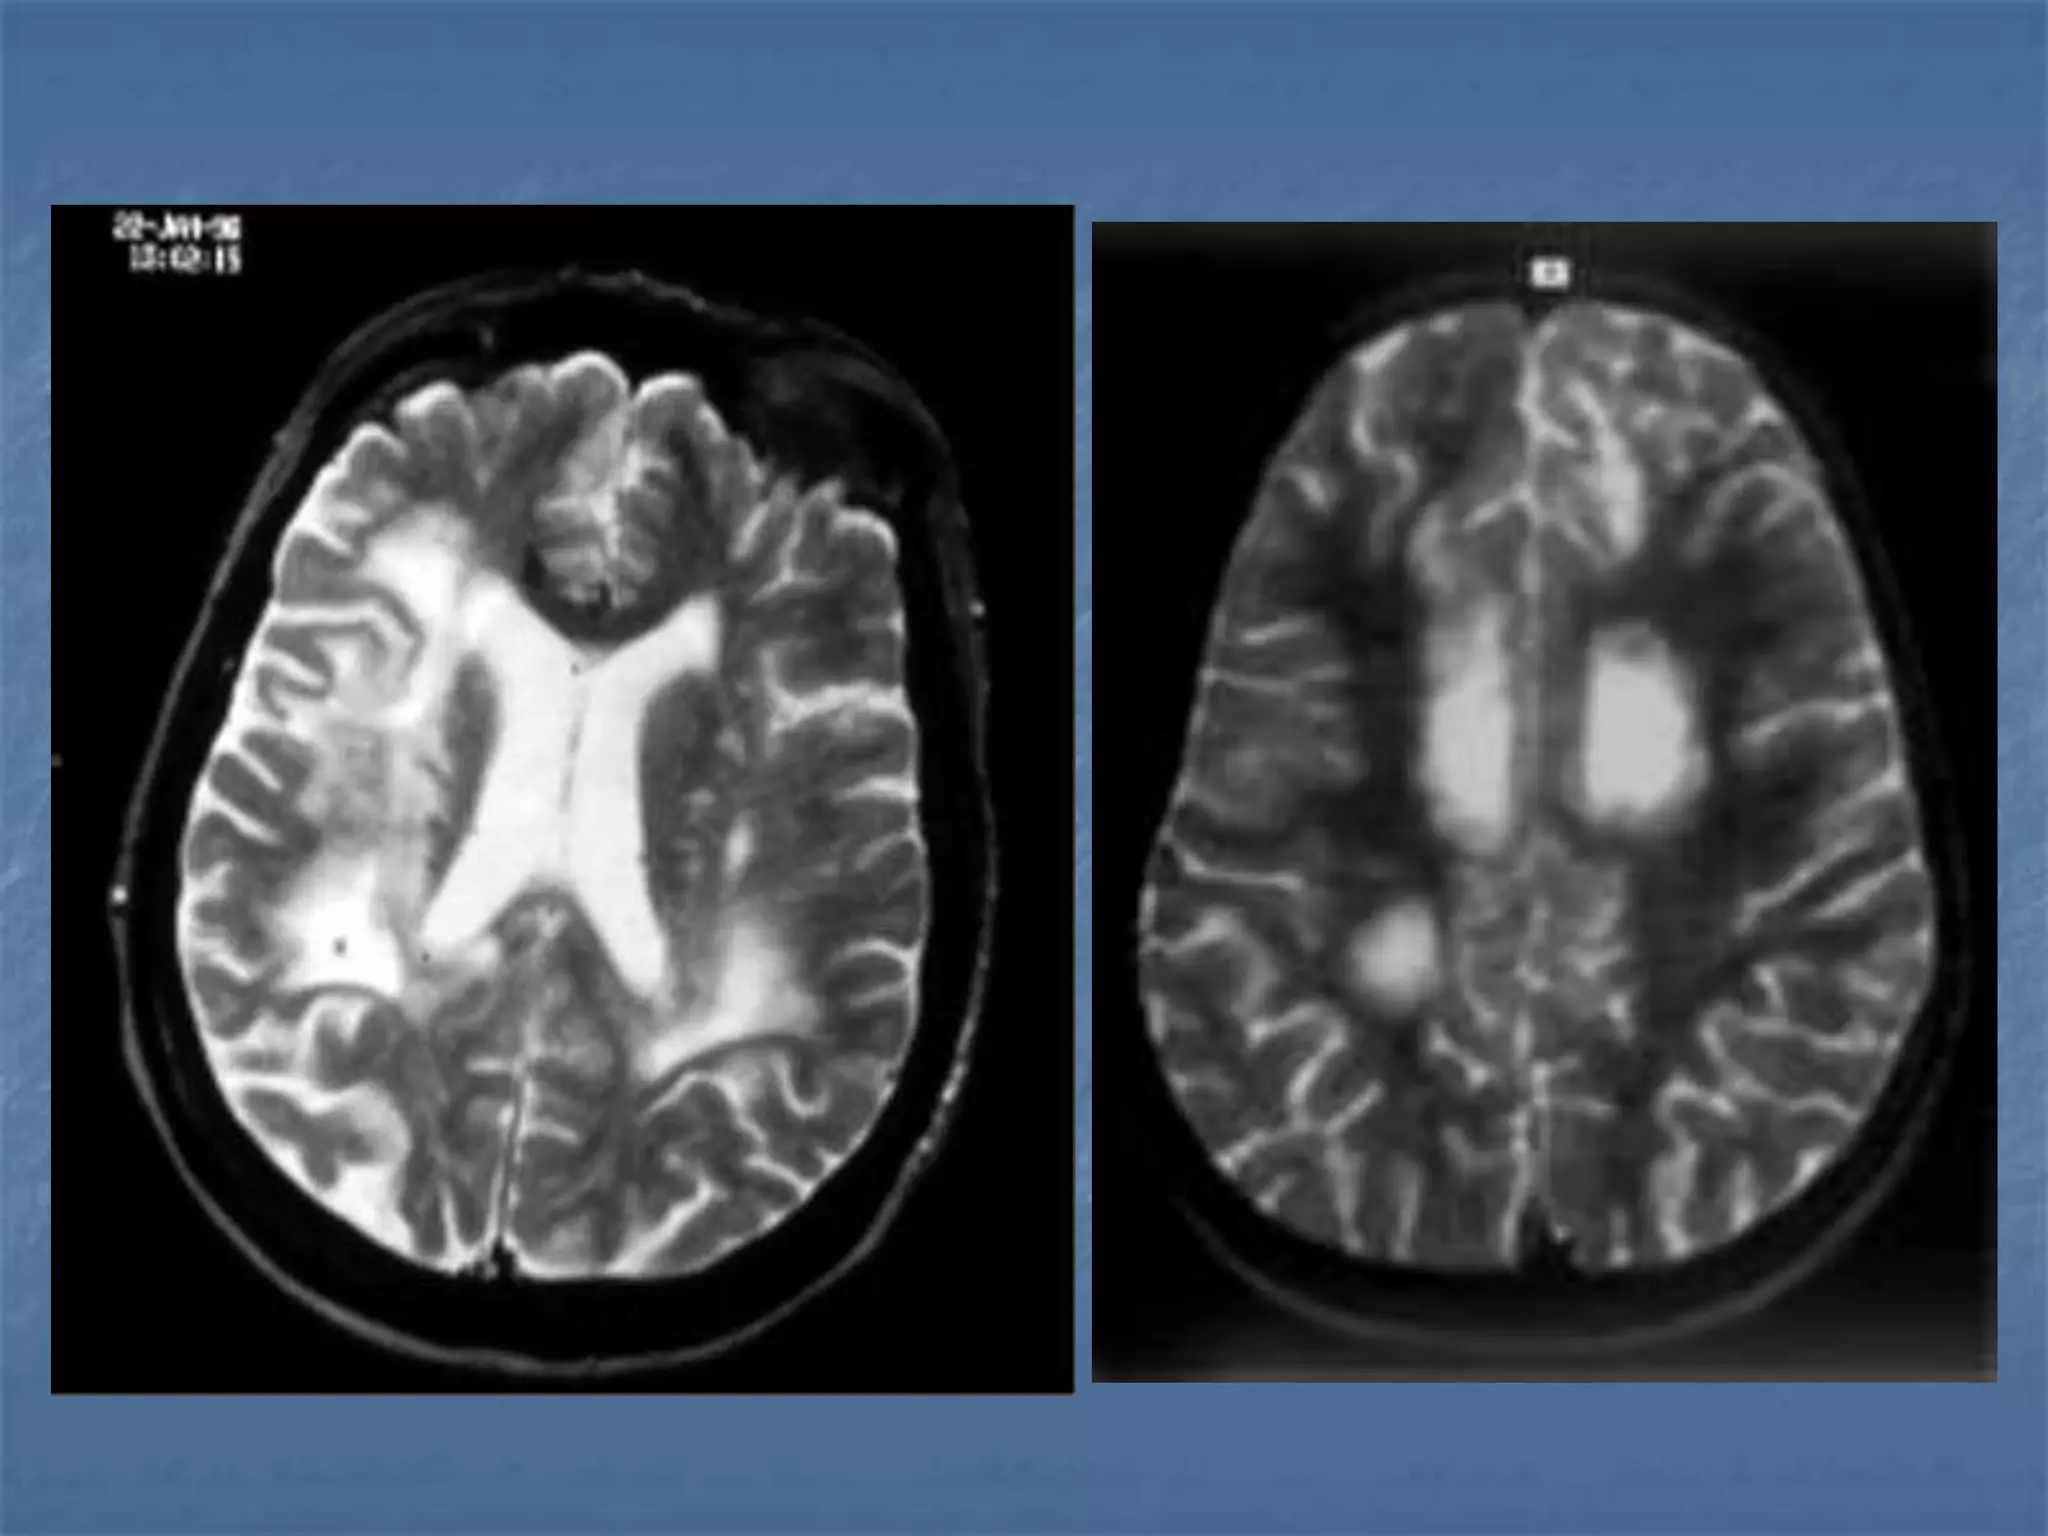

Lacunar Infarcts

Diffusion Weighted Imaging

Radiology 2000;217:331-345

Detects Infarct As

Early As 15-30

minutes

AJNR 2003 ;24:878-885